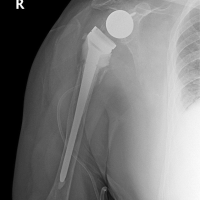

A 13-year-old girl presented to the outpatient department with intermittent pain in both hip joints for 6 months. Pain aggravated on prolonged walking and got relieved with rest and occasionally radiated to the inner thighs and knee. She had consulted a physician for hip pain and was prescribed symptomatic treatment without any further investigations. Since then, she was on intermittent painkillers but was able to do all the routine activities of daily life. The patient neither gave a history of any significant trauma nor of any underlying comorbidity that can affect bone metabolism. There were no obvious risk factors for the fracture too. Except for intermittent use of pain-relieving medications, she was not on any other medications and was not actively involved in any sports. Medical history, family history, and personal history were unremarkable. The build was normal for her age with a body mass index of 23.4 (normal range: 18.5–24.9). On clinical evaluation, the patient had a bilateral Trendelenburg gait with mild discomfort. The movements of both hips were painless and normal in range (flexion: 0–120°, extension: 0–10°, adduction: 0–30°, abduction: 0–40°, internal rotation: 0–30°, and external rotation: 0–30°) with no tenderness. There was no fixed deformity or limb length discrepancy and both limbs had normal neurovascular status. The laboratory tests that were conducted in the hospital did not reveal any significant abnormality except for a mild Vitamin D deficiency (Table 1).

The patient had normal rheumatological, metabolic, and endocrine workup. A radiograph of the pelvis with both hips showed a Delbet type II fracture neck of the femur with preserved neck length on both sides (Fig. 1).

There was varus angulation on both sides but no significant translation of the fragments. Neck shaft angles on the right and left sides were 98° and 99°, respectively; while Powel’s angles on the right and left sides were 57° and 65°, respectively (Fig. 2).

Computed tomogram (CT) scan of both hips confirmed a preserved neck length and alignment of fragments (Fig. 3). A diagnosis of bilateral stress fracture of the neck femur was made. Magnetic resonance imaging of both hips was done and the presence of osteonecrosis of the femoral head was ruled out. Under combined spinal and epidural anesthesia, the patient was taken on a traction table on both sides and both sides were operated in the same sitting, left followed by right. The fracture was reduced satisfactorily by a closed maneuver. However, as Powel’s angle was high on both sides, valgus osteotomy was planned at the sub-trochanteric level with an aim of getting 30° corrections in Powel’s angle on both sides. A guide wire was passed across the fracture from the lateral cortex of the trochanter at an angle of 100° to the long axis of the femur. Fixation of the fracture was done with a 9.5 mm dynamic hip screw (DHS). Thereafter, valgus sub-trochanteric osteotomy was performed on both sides and fixation was done with a 130° side plate (Fig. 4).